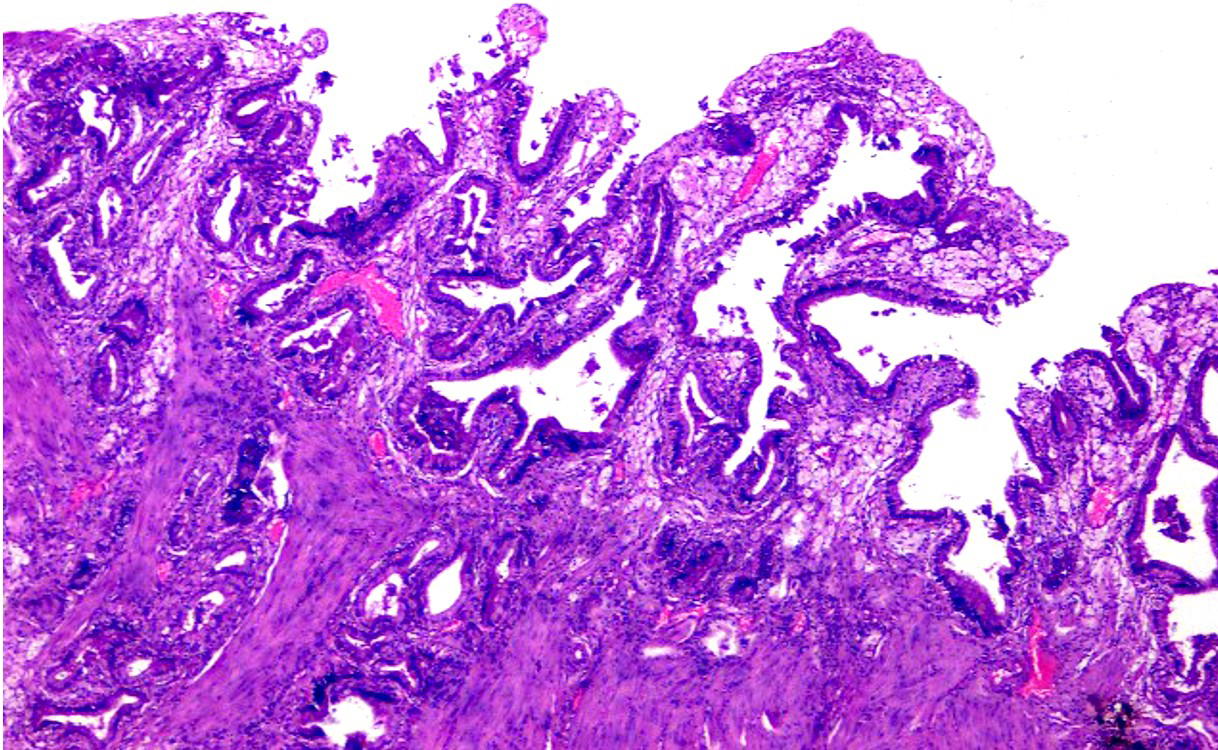

A 32-year-old male presented with mild to moderate pain in the right upper abdomen for 4 years that was increased after the spicy and fatty meal. He is a non-vegetarian, but mostly consumed vegetarian foods. During the past six months, he also experienced several episodes of vomiting after severe pain attacks. There was no history of any addiction like smoking, alcohol, etc. Gallbladder (GB) ultrasound showed well distended GB, normal wall thickness, and a single stone in its lumen (Figure 1).  Acute calculous cholecystitis diagnosis was made based on history, examination and USG, and the patient was referred to us for laparoscopic cholecystectomy. When the patient was admitted, his vital signs were stable: his oral temperature was 98.40 F, pulse rate was 76 per minute, blood pressure was 110/70 mmHg, and his respiratory rate was 18 per minute. On examination, the right hypochondrium was tender. On deep palpation, the pain got aggravated and no lump or organomegaly was detected. The systemic examination was normal and no abnormality could be detected. Chest X-ray and ECG were also normal. The laboratory blood biochemistry and serology parameters were also within normal limits.

Figure 1 USG of Calculus Cholecystitis.

Another school of thought is that cholesterolosis is caused by defects in macrophages that are no longer able to metabolize and excrete cholesterol absorbed from bile. Though the diagnosis by ultrasonography is difficult when these deposits get bigger in size, they can be well detected by the USG (Figure 4).4 The Spectrum of Clinical presentation is wide from the silent finding without any symptom to free-floating biliary sludge to pain in the right upper abdomen due to acalculous cholecystitis to calculous cholecystitis with cholesterol stones.5 Laparoscopic cholecystectomy should be considered as the treatment of choice in symptomatic patients of gallbladder cholesterolosis.

Figure 4 USG of Acalculus Cholecystitis with thickened GB wall studded with the cholesterol crystals..